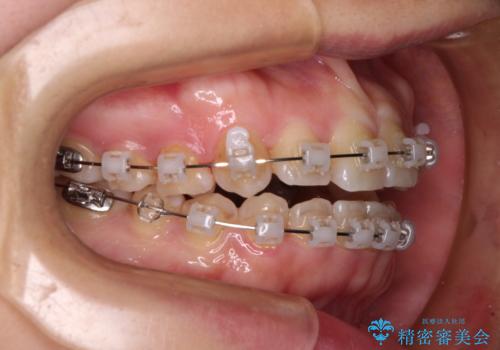

- クリアブラケット

- 1年7ヶ月

- 10-30回

舌の突出癖により上下前歯が開咬となりましたが、舌のトレーニングと顎間ゴムの使用により、元々の被蓋関係に改善することができました。

アンカースクリューを用いて、出っ歯仕上がりを回避し、正中位置も改善することができました。